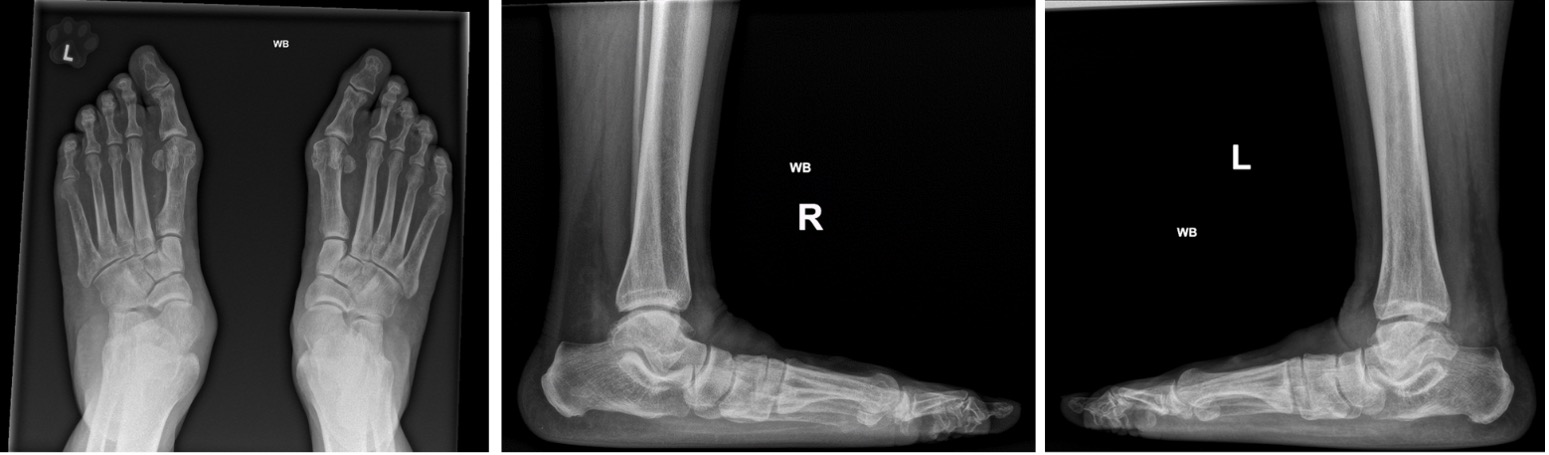

- Weightbearing AP and lateral, oblique foot radiographs (Fig 7); assess for:

- Talo-first-metatarsal alignment on AP and lateral (Meary’s angle)

- Apex of deformity

- Talonavicular coverage angle

- Calcaneal pitch angle

- Arthritic changes

- Other deformities (hallux valgus)

- Weightbearing AP and lateral ankle radiographs

- Assess for tibiotalar valgus deformity and arthritic changes

Figure 7: Standing AP, oblique and lateral showing talar head uncovering and loss of Meary’s angle (J&S Stage IIA disease)

Figure 8: Standing AP and lateral showing bilateral talar head uncovering and loss of Meary’s angle (J&S Stage IIB disease)